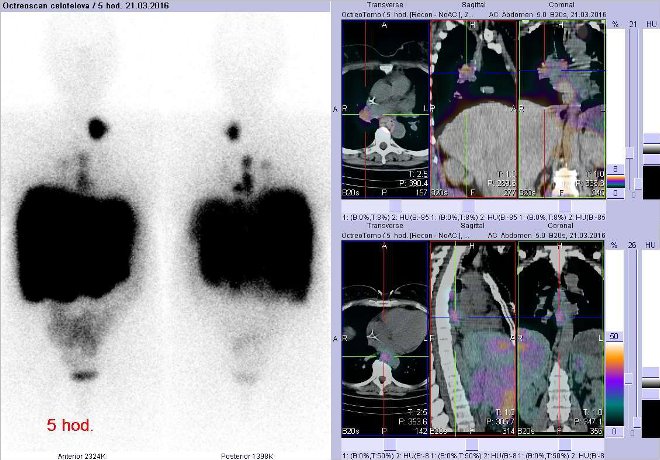

/ Obr. č. 1: Celotělová scintigrafie v přední a zadní projekci s dvojí modulací obrazu.

Vyšetření 5 hod. po aplikaci radioindikátoru.